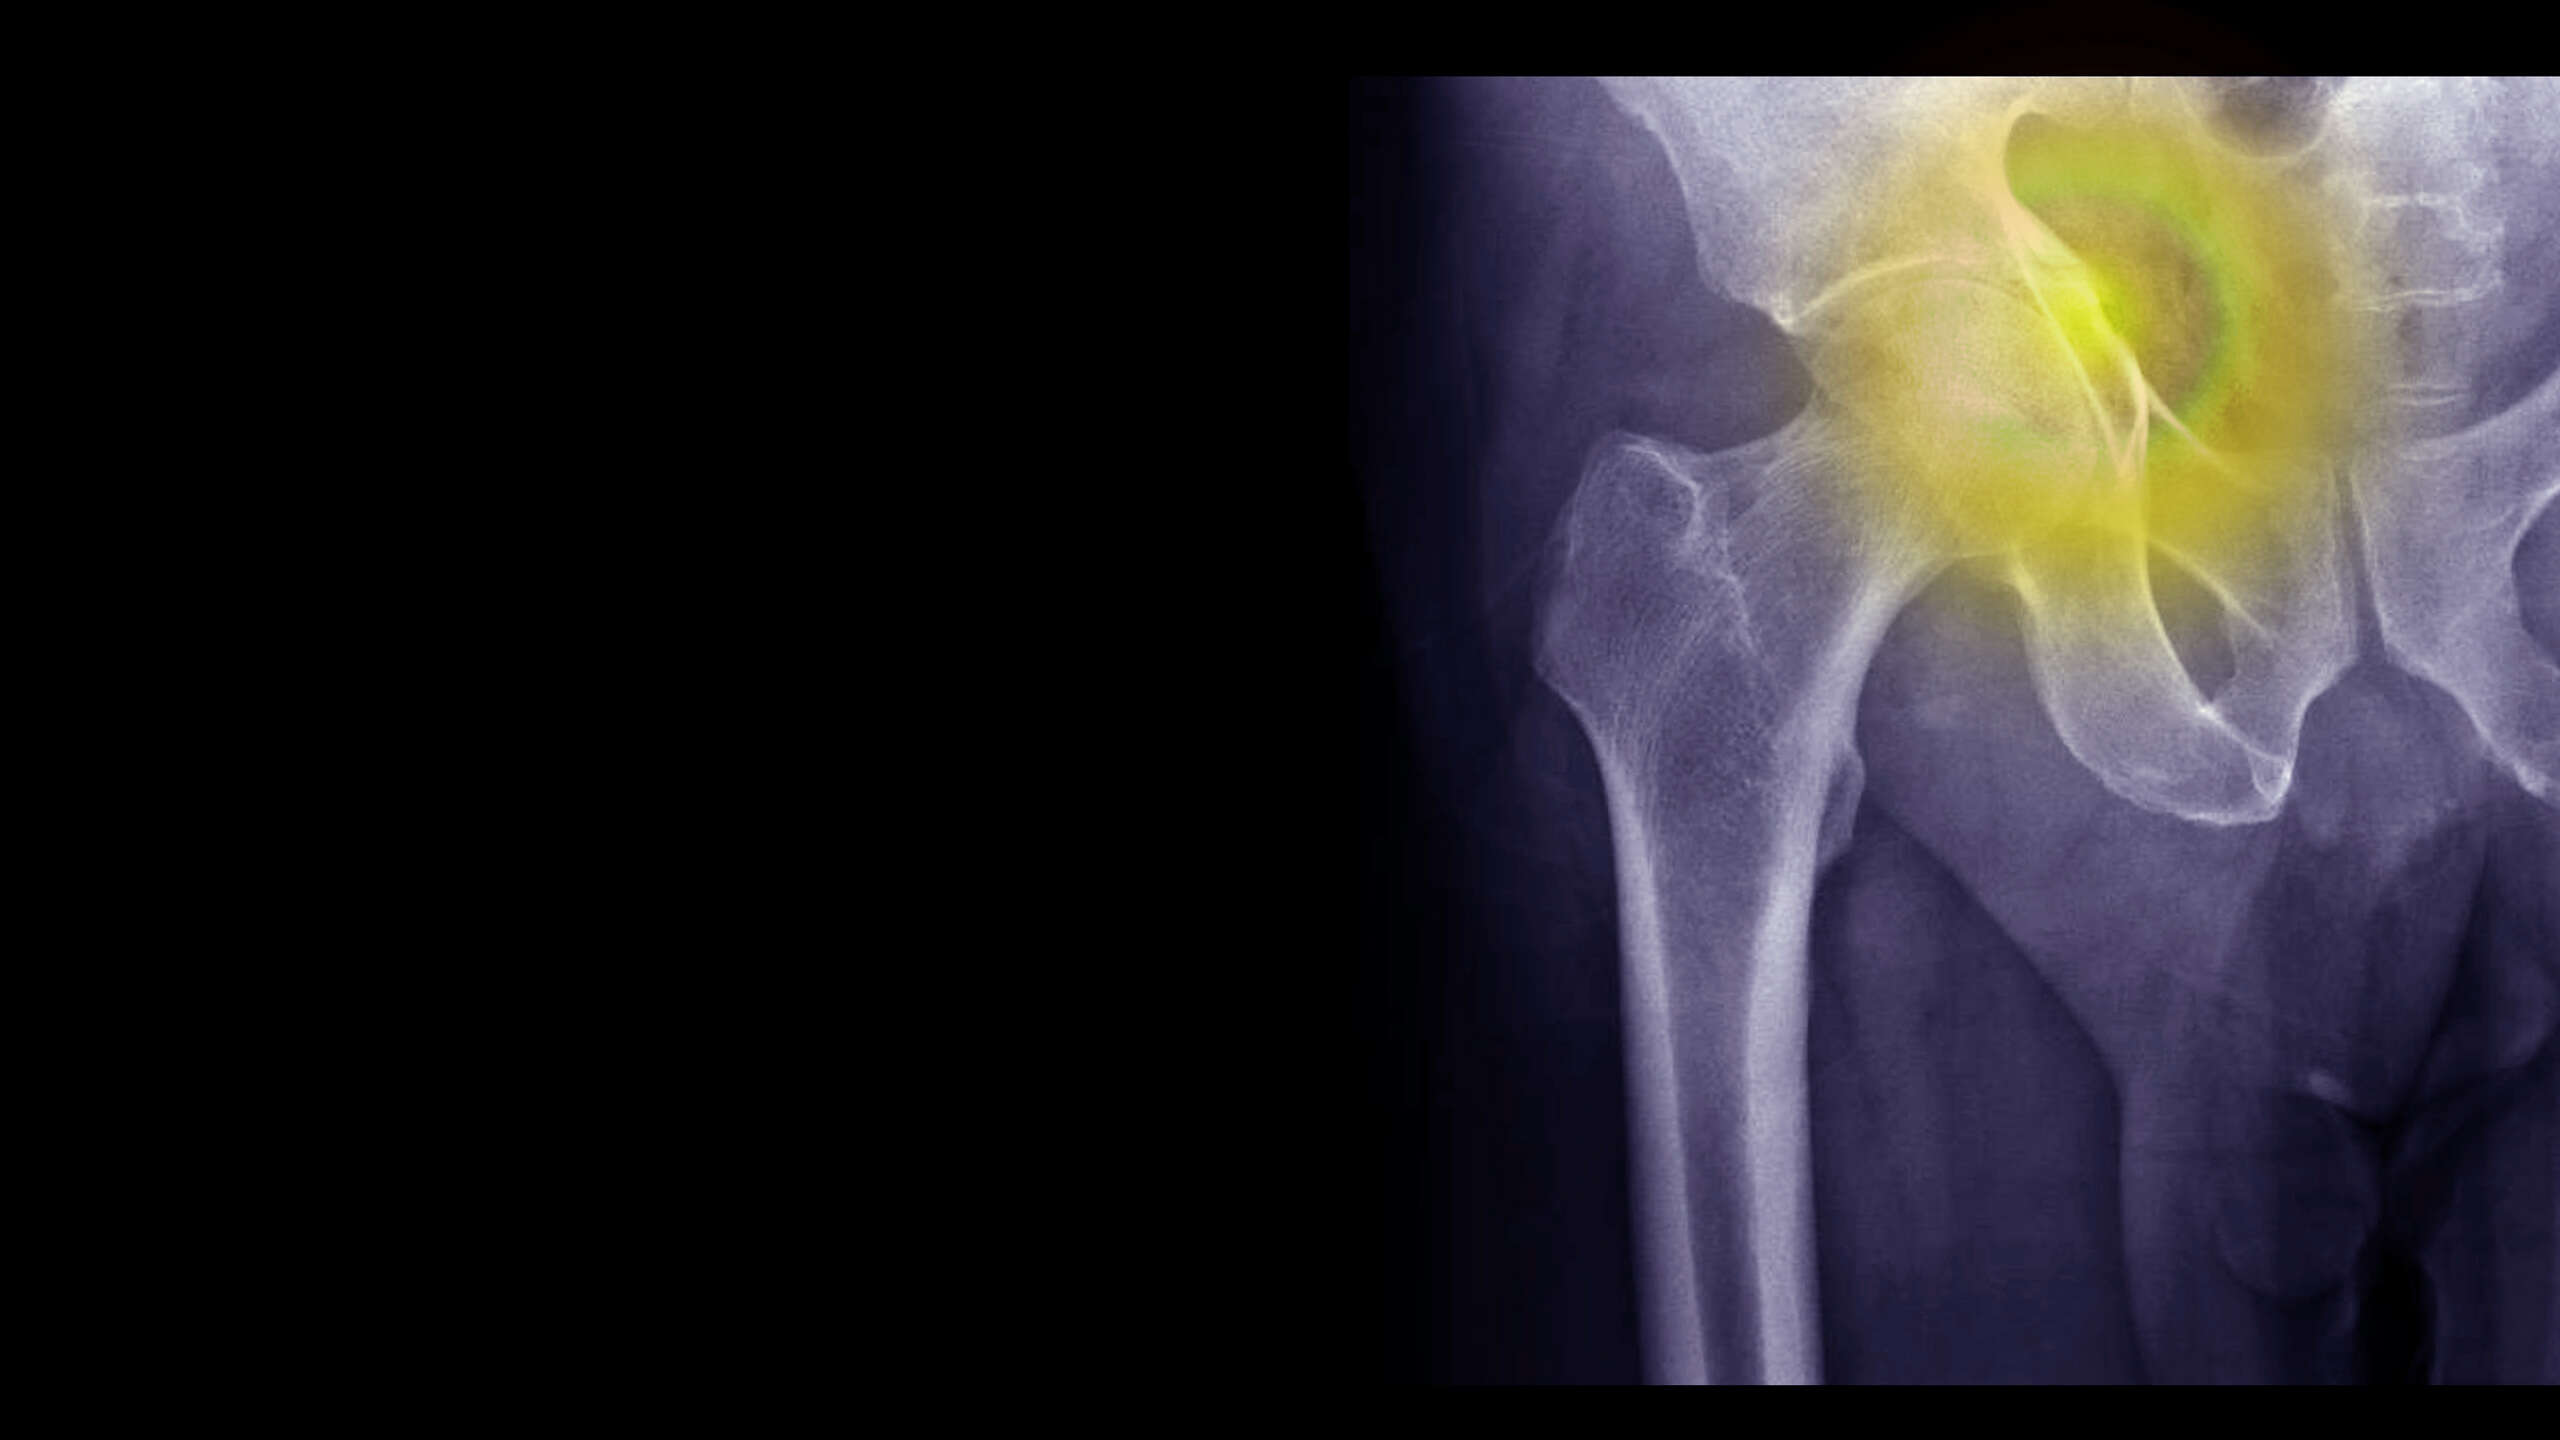

Dokładna diagnostyka złamania wymaga konsultacji ze specjalistą i przeprowadzenia diagnostyki obrazowej. Rutynowo w tym celu wykorzystuje się badanie rentgenowskie, które pozwala uwidocznić miejsce i przebieg złamania. Klasyczne złamania mogą dotyczyć w zasadzie każdej kości, choć zwykle występują w kościach długich, np. rąk lub nóg.

Czym wyróżniają się osteoporotyczne złamania kości?

Obok klasycznego podziału złamań wyodrębnia się także złamania osteoporotyczne. Są one wynikiem zmniejszenia gęstości masy kostnej (ang. BMD, Body Mass Density) wskutek rozwijającej się osteoporozy.

Nie wypracowano jednej powszechnie przyjętej definicji złamań osteoporotycznych. Inaczej mówiąc, są to złamania niskoenergetyczne. Pod tym pojęciem zwykle rozumie się złamanie u dorosłego po 40. roku życia po niewielkim urazie, którego nie doznałby zdrowy szkielet. Niekiedy też można spotkać się z wyjaśnieniem, że złamania osteoporotyczne zdarzają się w trakcie wykonywania czynności życiowych, którym towarzyszy upadek z wysokości nie większej niż własnego ciała.

Ze względu na lokalizację złamań osteoporotycznych, najczęściej występują one w następujących obszarach:

• biodro,

• kręgosłup.